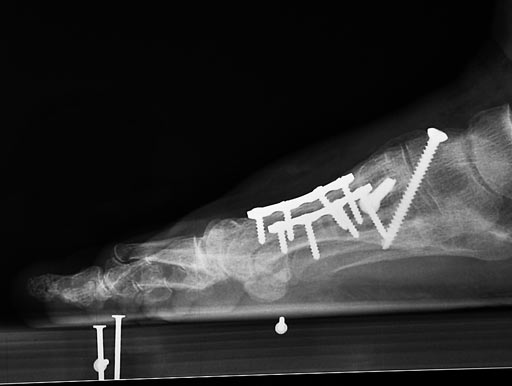

LC-DCP Adaption Plate for metatarsal osteotomy

The LC-DCP Adaption Plate 2.4 with four holes is an addition to the existing implants and instruments of the Modular Foot Set 2.4.

The LC-DCP Adaption Plate 2.4 is indicated for treatment of fractures and osteotomies on the 2.4. metatarsal bone. The need for compression and the possibility of movement of the plate is very important for these procedures, therefore the DC-hole is more advantageous compared to the LCP. The standard DCU hole allows for 1480 of angulation and enables compression on both directions.

Furthermore, the plate has a scalloped contour providing a better view to the bone.

Plate in situ after corrective osteotomy and arthrodeses

Case provided by Kaj Klaue, Switzerland.